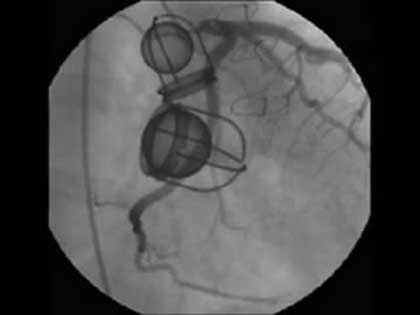

Bihotzeko bi balbula artifizial horiek grabatu zituzten 67 urteko emakume baten bihotzean Kanadako Montreal Bihotz Institutuan. Bihotzaren bi irteera-tututan jarri zizkioten orain dela hogeita hemezortzi urte, odolak atzera egitea saihesteko. Dagokien bihotz-barrunbearen presio-aldaketak eragiten du ikusten diren pilotatxoek kaiolan aurrera edo atzera egitea, eta, hala, odolari pasatzen uztea edo atzerako bidea oztopatzea.

Hogeita hemezortzi urte hauetan guztietan ez dute hutsik egin, baina balbulak zahartzen hasiak dira dagoeneko. Emakumea ospitalera joan zen, nekez hartzen zuelako arnasa. Han, kateterismo bat egin zioten bihotzean, gauzak behar bezala ote zeuden ikusteko, eta erabilitako kontrasteari esker lortu zituzten orain ikusgai ditugun irudiak.